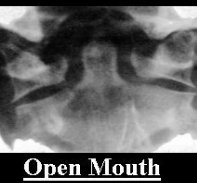

C Spine

Click on image (To learn how to assess C-spine Xrays)

Atlas dens interval (ADI) - < 3 mm adult < 5 mm child

Wackenheim line - extension back of clivus, within 1 to 2mm of dens tip

Spinolaminar line C1 to C3 - within 2 mm

Space available for cord (SAC) - > 13mm adults